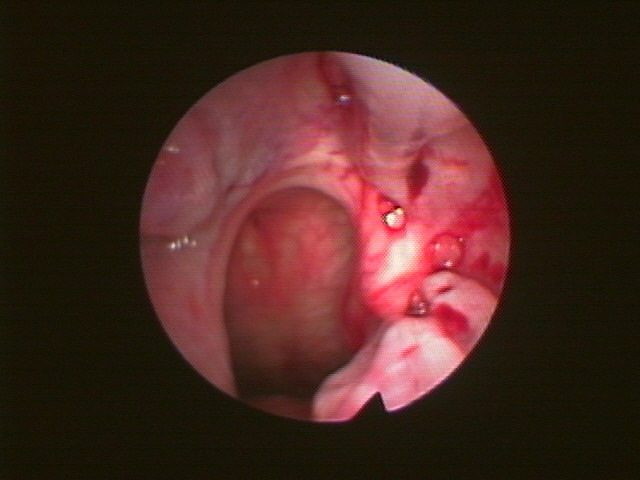

・お年寄りでは鼻の後ろの血管が突然に破れて、大出血することがあります。特に高血圧や動脈硬化のある人に多くみられます。

・鼻の後ろからの出血はなかなか止まらないことが多いので、医師を受診しましょう。